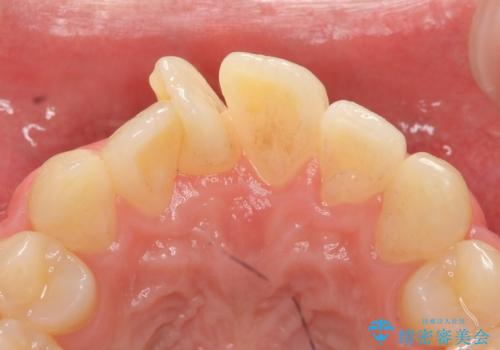

- 上顎前歯の歯並びが気になるが仕事が忙しく矯正治療は難しいため、セラミック矯正で綺麗にしたいといらっしゃった方の症例です。

左右の1番目の歯は傾きが大きいため、セラミッククラウンにするにあたり神経治療を行うことを御了承頂いた上で、前歯4本をオールセラミッククラウン(スペシャル)により補綴しました。